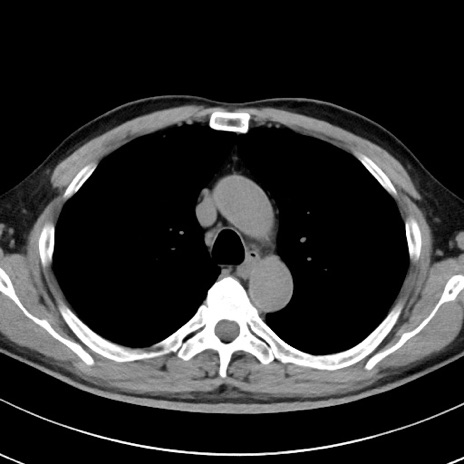

【腹部TIPS】症例29 参考症例 CT(横断像)

症例

70歳代男性